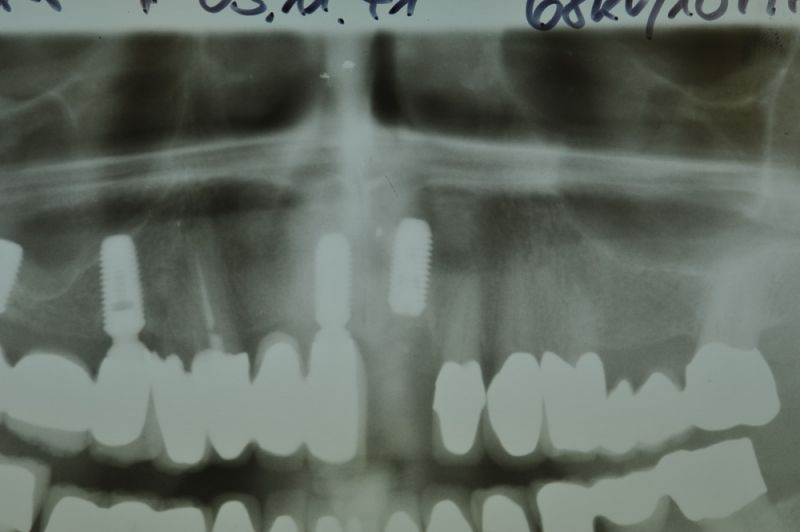

Kieler Patient erhält implantatgetragene Frontzahnbrücke

Dieser Patient fällt ein bißchen aus dem üblichen Rahmen, weil die vielfachen Versorgungen hier nicht zeigtlich im Rahmen einer CMD Behandlung erbracht wurden, sondern über viele Jahre hinweg nach und nach.

Der Patient wurde von dem Praxisvorgänger übernommen und befindet sich daher seit weit über 20 Jahren hier in Behandlung.

Dieser Patient hat keine funktionellen Beschwerden und aufgrund der geschilderten Vorgehensweise war es niemals Ziel der Behandlung die bestehenden Bissverhältnisse zu untersuchen, oder therapeutisch zu verändern, weil der Patient zu den Patienten gehört, die mit einem fehlerhaften Biss, wir nennen es Habituelle Okklusion, keinerlei Probleme und Beschwerden hat.

Was man an diesem Fall gut zu erkennen vermag, dass Patienten, die für sich irgendwann entschieden haben, nicht mit einem herausnehmbaren Zahnersatz ihren Lebensabend verbringen wollen auch nach und nach auf eine Implantatpfeilerstützzahl kommen, die genügend Substanz für die Lebensphase bieten, in der körpereigene Stützsubstanz, in Form von Zähnen zunehmend verloren geht.